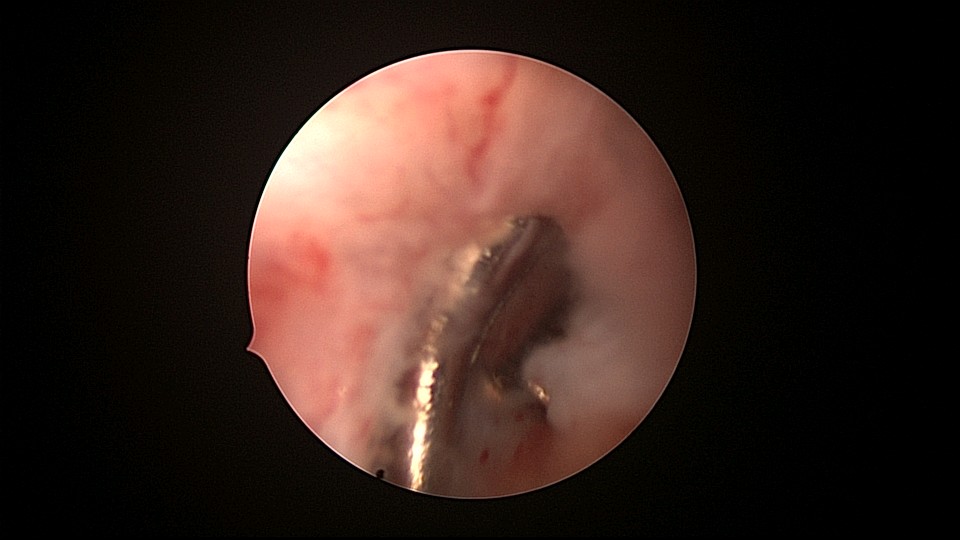

患者81岁,G5P5,顺产5次,安环50年,绝经23年,高血压病史多年,10年前因颅内肿瘤行开颅手术,4年前行腹腔镜胆囊切除术,外院介绍到我院宫腔镜取环。子宫前位,宫颈萎缩,穹隆展平,宫颈外口位于穹隆偏左侧,平滑狭小,夹持宫颈很困难,阴道内镜方式进入宫腔,见宫腔下部O型环圈内前后壁粘连,顿性分离粘连,宫腔中上部O型环与两侧宫壁嵌顿,异物钳松动节育环,但难以取出,取环钩沿镜鞘外侧进入宫腔,配合中弯钳牵拉出节育环,环变形,检查环完整,宫腔无其他异常。